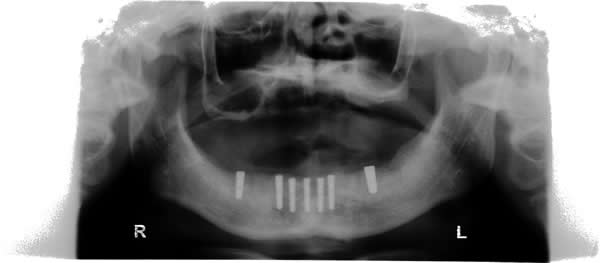

Implant Stage.... Fixed Bridge will be supported by 7 implants.